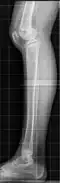

Genu recurvatum, česky pokřivené koleno, zakřivené koleno, otočené koleno nebo jen křivé koleno, je vzácná patologická deformita kolenního kloubu (articulatio genus). Je charakteristická tím, že se koleno ohýbá opačným směrem než je pro člověka obvyklé. Může mít různé stupně závažnosti.[1][2]

Bližší popis

Rtg. snímek -